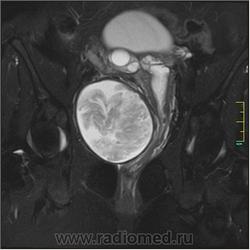

Госсипибома.

Госсипибома, или текстилома - это название группы осложнений после хирургических вмешательств в результате оставленных в теле пациента инородных предметов. Термин "Госсипибома" состоит из латинского слова gossypium (хлопок) и слова из языка суахили boma (место, где что-то спрятано), по другим данным - греческого "oma" - частицы, обозначающей опухоль. Так или иначе, госсипибома представляет собой матрикс из хлопка, окруженный гранулемой инородного тела. Термин текстилома появился позже и стал использоваться вместо термина "госсипибома", когда в хирургии вместо хлопка начали применять синтетические материалы.

Ж, 35 лет. Состояние после субтотальной гистерэктомии без придатков по поводу осложненных родов около полугода назад. Обратилась на МРТ в связи с болями и неприятными ощущениями в области малого таза.

Вот такая картинка.